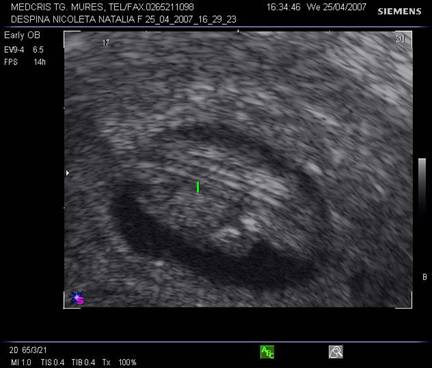

Fig nr. 8. Sarcina 5 sapt la ecografia transvaginala :sac ovular cu vezicula vitelina evidenta marcata cu sageata, retrouterin ovar chistic

Fig nr.9. Vezicula vitelina, marcata cu sageata, la ecografia transvaginala, sarcina 5 sapt.